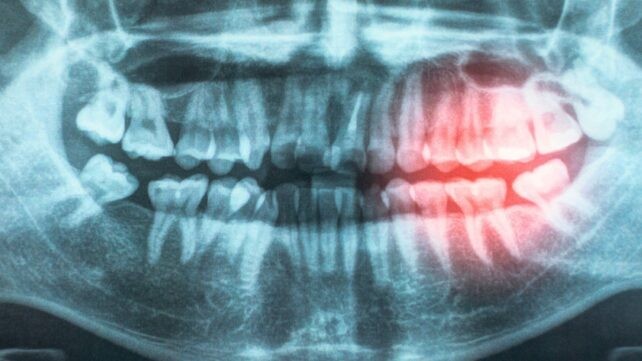

Eine Übersichtsarbeit der American Heart Association Cardiovascular Disease Prevention Committee stützt die These, dass die Mundgesundheit zum Schutz vor Herzkrankheiten beiträgt. Aus einem Jahrzehnt an Literatur, das genetische Untersuchungen, klinische Studien und Labortests umfasst, aktualisiert ihr Bericht die 2012 veröffentlichte wissenschaftliche Stellungnahme und liefert noch stärkere Belege dafür, dass Herzprobleme, die durch verengte Arterien verursacht werden (atherosklerotische kardiovaskuläre Erkrankung, ASCVD), eng mit Parodontitis verbunden sind. Im Rahmen ihrer Überprüfung untersuchten die Forscher mögliche Gründe für die Verbindung, einschließlich der Wahrscheinlichkeit, dass Bakterien durch freigelegtes und beschädigtes Zahnfleisch in den Körper gelangen und chronische Entzündungen verursachen. ASCVD bleibt die weltweit führende Todesursache, und wenn eine Verbesserung der Mundhygiene möglicherweise eine Möglichkeit wäre, ASCVD aufzuhalten, lohnt es sich, das weiter zu untersuchen. Einige der analysierten Studien reichten bis in die Kindheit zurück und fanden heraus, dass die Pflege der Zähne in jungen Jahren das Risiko für Herzprobleme später im Leben senken könnte.

Eine der zentralen Annahmen lautet, dass Bakterien aus entzündetem Zahnfleisch in den Blutkreislauf gelangen können und dort chronische Entzündungen auslösen, die Blutgefäße schädigen und das Risiko für Herzkrankheiten erhöhen. „Ihr Mund und Ihr Herz sind verbunden“, sagt der pädiatrische Kardiologe Andrew Tran. „Parodontitis und schlechte Mundhygiene können Bakterien in den Blutkreislauf gelangen lassen, wodurch Entzündungen entstehen, die Blutgefäße schädigen und das Risiko von Herzerkrankungen erhöhen.“ Verwandt: Studie verknüpft Zahnerkrankungen mit weißer Substanz im Gehirn.

Es gibt starke Hinweise darauf, dass die Behandlung von Parodontitis Zwischen-Ergebnismessgrößen wie Blutdruck, HDL-Cholesterinwert und Entzündungsmarker verbessert, schreiben die Forscher in ihrer veröffentlichten Arbeit. „Es gibt starke Belege dafür, dass die Behandlung von Parodontitis Zwischen-Ergebnismessgrößen wie Blutdruck, HDL-Cholesterinwert und Entzündungsmarker verbessert,“ heißt es in der Veröffentlichung. „Dies ist eine wichtige Erkenntnis, weil diese Messgrößen dafür bekannt sind, das zukünftige kardiovaskuläre Risiko zu erhöhen und eine mögliche Verbindung zwischen Parodontitis und ASCVD liefern.“ Das Gremium hinter der neuen Forschung fordert detailliertere und längerfristige Studien, um die bestehende Forschung zu Herzkrankheiten und Mundgesundheit weiter auszubauen, einschließlich der Frage, ob Behandlungen für etablierte Parodontitis die Wahrscheinlichkeit von ASCVD verringern. Darüber hinaus betonen sie, dass es neben dem Herzen auch andere Vorteile gibt, die mit guter Mundhygiene einhergehen, einschließlich seltenerer Zahnfüllungen. Frühere Forschungen haben zudem eine Verbindung zwischen einem sauberen und gesunden Mund und Zuständen wie Diabetes und sogar Krebs hergestellt.